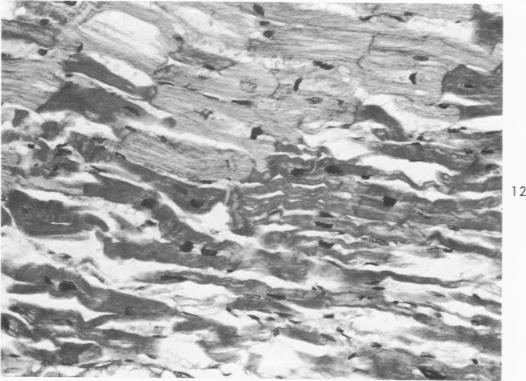

The histopathology of human myocardial infarcts is reviewed in a series of 46 cases ranging from sudden death to a clinical age of 3 days. A set of histopathologic features is described whereby the diagnosis of acute myocardial infarction can be made, even in cases of sudden death, on routine sections and even after considerable autolysis. This is primarily a stretching and waviness of the myocardial fibers, especially at the border of the infarcted area. Its mechanism is probably twofold: the rythmical pull exerted by the normal myocardium against the infarcted paralyzed area and the outward bulging of this area at every systole. On the basis of human material alone, it may be inferred that this pattern develops very rapidly: surely less than 1 hour and perhaps a few minutes after the local circulation has failed.

回顾了46例人类心肌梗死的组织病理学情况,这些病例涵盖了从猝死到临床病程3天的患者。描述了一组组织病理学特征,据此即使在猝死病例中,通过常规切片,甚至在经历相当程度的自溶后,也能够作出急性心肌梗死的诊断。这主要表现为心肌纤维的伸展和波纹状,特别是在梗死区域的边界处。其机制可能是双重的:正常心肌对梗死的麻痹区域施加的节律性牵拉,以及该区域在每次心脏收缩时向外膨出。仅基于人体材料就可以推断,这种形态发展非常迅速:肯定在局部循环停止后不到1小时,也许几分钟内就会出现。